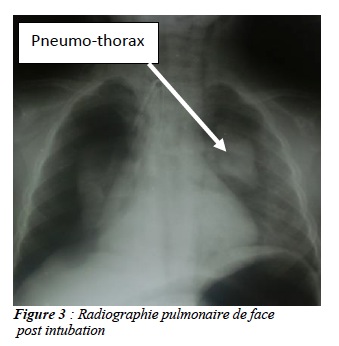

L’indication d’une trachéotomie de sauvetage a été posée et celle-ci réalisée après une intubation orotrachéale. La laryngoscopie avant mise en place de la sonde d’intubation n’a pas permis de visualiser le corps étranger. L’évolution immédiate a été marquée par une reprise ventilatoire. Les suites opératoires post-trachéotomie on été marquées par la persistance de la dyspnée, et l’abolition du murmure vésiculaire dans le champ pulmonaire droit. La radiographie pulmonaire de contrôle a mis en évidence le corps étranger dans la bronche souche droite associé à un pneumothorax (Fig : 3).